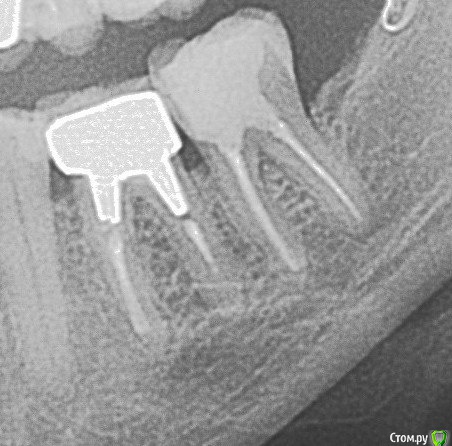

igorstom Опубликовано 19 ноября, 2017 Автор Поделиться Опубликовано 19 ноября, 2017 Подведу итог своим изысканиям. Кратко. Каналы пройдены и расширены... Коффердам, каналы обрабатываю лимонкой, гипохлоритом (если не получается герметично работать хлоркой заменяю на хлорофиллипт), и заполняю гидроокисью. Через несколько подобных процедур (зависит от многих факторов, но обычно не более 2-4 раз) в последний прием - вымываю гидроокись 3% перекисью, импрегнация спиртовым хлорофиллиптом при помощи бумажного штифта, пломбирую латеральной конденсацией гуттаперчей с Адсилом. Временная повязка из СИЦ. Горячей гуттаперчи к сожалению нет. Всё! Никого не призываю повторять, не рекламирую. Я так работаю. Может через некоторое время что-то изменю. Но пока всё устраивает. 1 Ссылка на комментарий